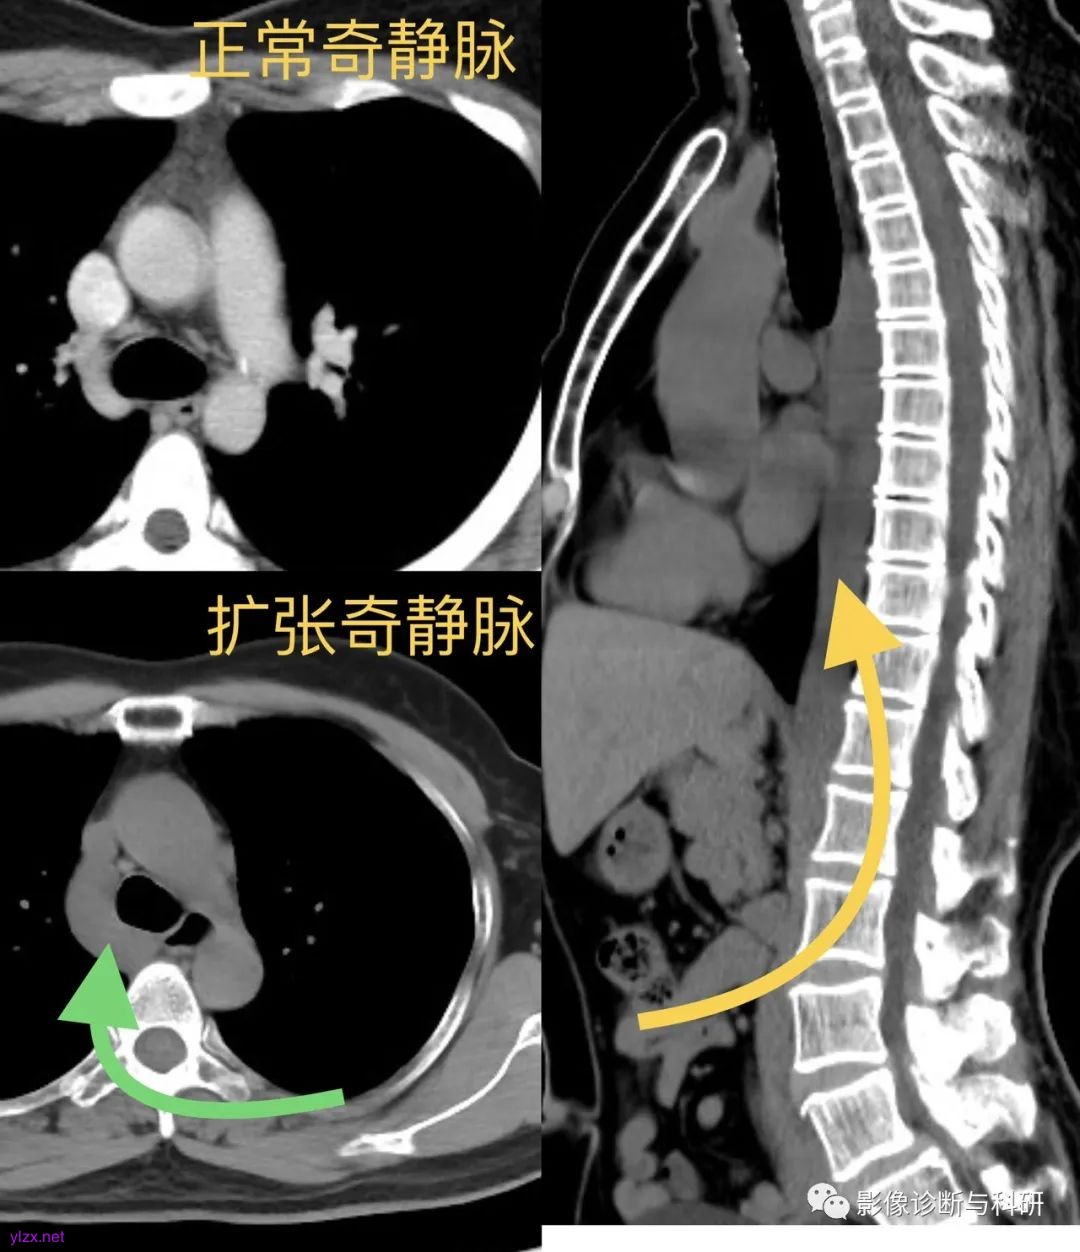

四、奇静脉扩张

引起奇静脉扩张的原因主要是两个方面:

一是患者的右心房压力突然增高。

当右房压力增高如肺动脉高压、主动脉夹层、动脉瘤、右心功能衰竭或大量心包积液时,右房的压力传导至上腔静脉及奇静脉,引起奇静脉压力增高,同时还阻碍静脉血回流至上、下腔静脉,奇静脉血流量增加,从而引起奇静脉扩张。

二是患者体内的奇静脉血流量增多。

当患者下腔静脉出现病变如下腔静脉栓子时,大量的静脉血通过奇静脉回流至上腔静脉,从而引起奇静脉扩张;当患者出现门静脉高压时,门体分流侧支循环开始建立,已经曲张的食管旁静脉与食管静脉会间接或者直接进入奇静脉,增加了患者奇静脉内部的血液流量,从而导致奇静脉扩张。另外奇静脉、半奇静脉与腰静脉、腰升静脉及左肾静脉都有交通支,因此当左肾静脉压迫或狭窄时,左肾静脉的血液可经这些交通支与奇静脉相连,从而使奇静脉压力增高且血流量增多。而先天性变异所导致的布加综合征患者形成一系列肝内及肝外侧支循环,其中有2条吻合支通过腰升静脉、奇静脉、半奇静脉系统,最终血液进入右心房,奇静脉成为最重要的侧支。